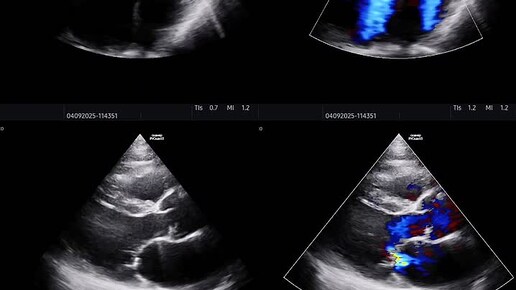

Значительная митральная и трикуспидальная регургитация